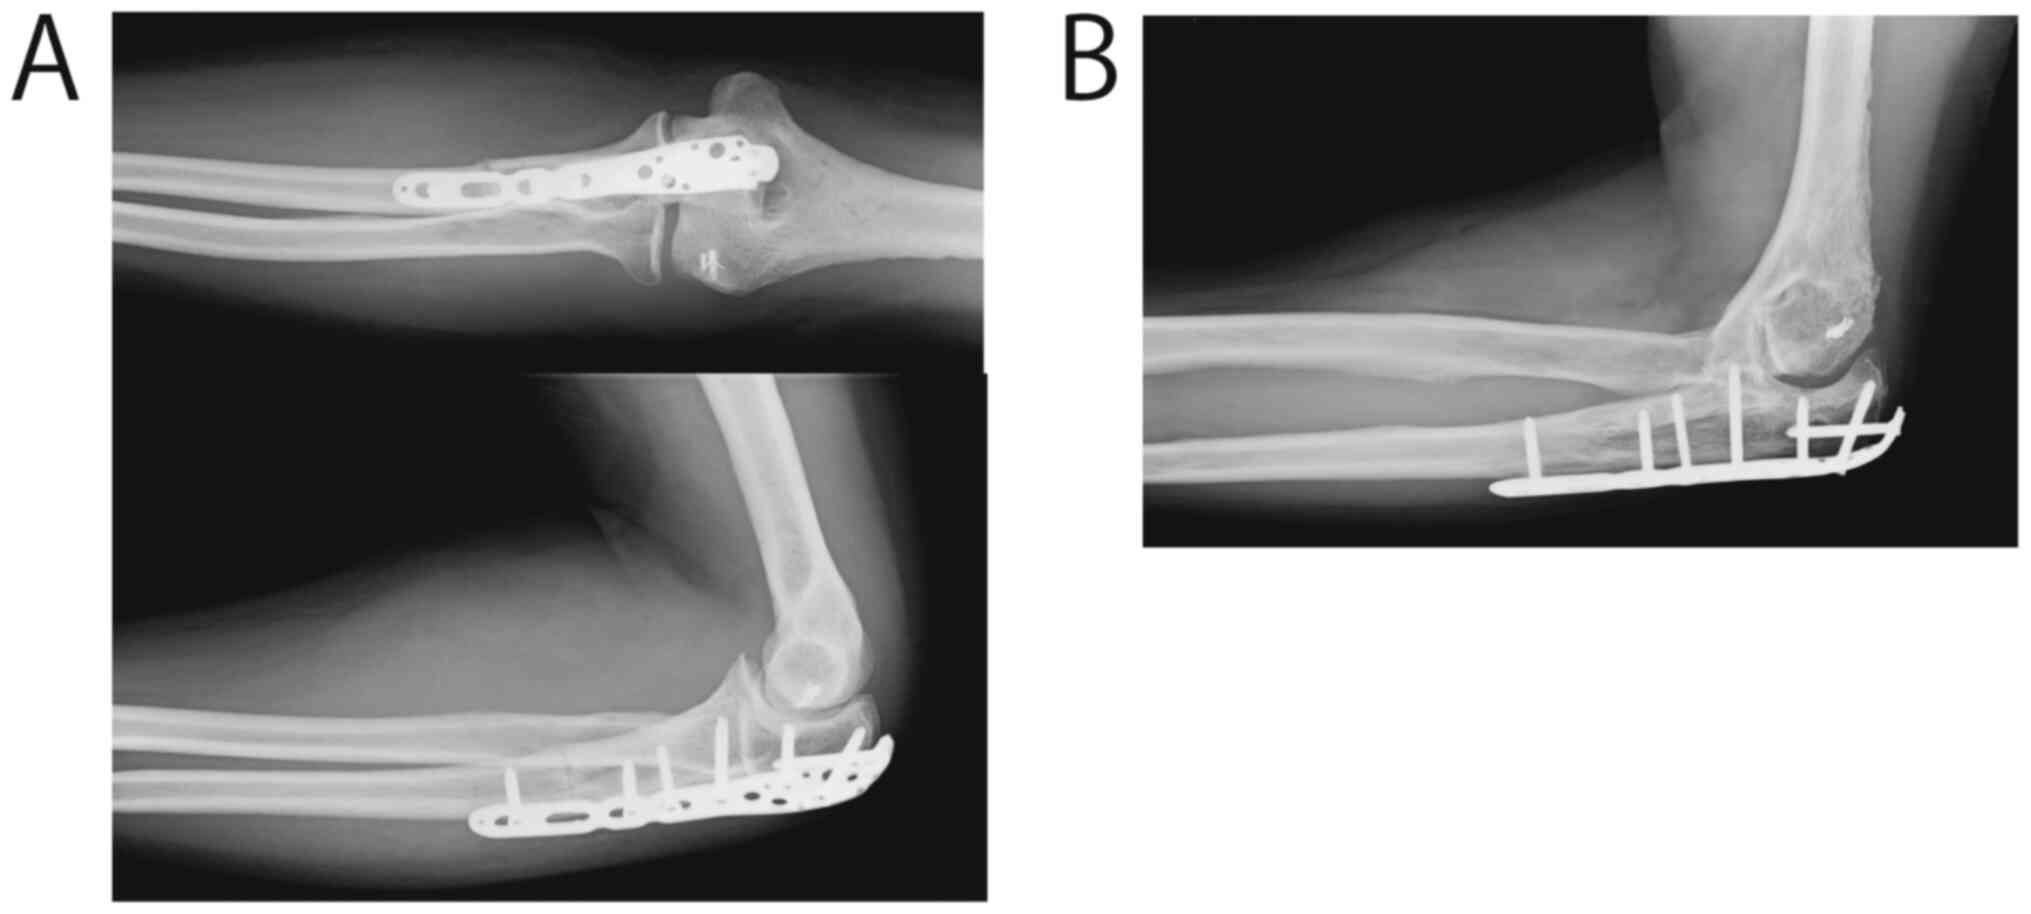

Reconstruction Of The Elbow Using Pedicle Joint Freezing After Wide

Reconstruction Of The Elbow Using Pedicle Joint Freezing After Wide